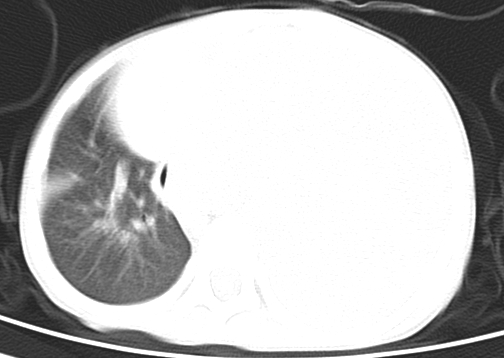

患儿 女 4岁,发热 咳嗽 胸透 考虑:左侧脓胸

左侧胸廓内见大量密实阴影,肺尖部尚有少量肺组织影,纵膈明显受压移位,肋骨未见明显受侵征象,虽然病人年龄较小,但如此大量的“积液”,还是要警惕,不同意一般感染,可结合穿刺脱落细胞学检查。

1)考虑左肺炎症感染。2)左侧大量胸腔积液。

1)考虑左肺炎症感染。2)未经穿刺只能定左侧大量胸腔积液。

左侧张力性大量胸腔积液压迫性肺不张、感染;建议治疗后复查。